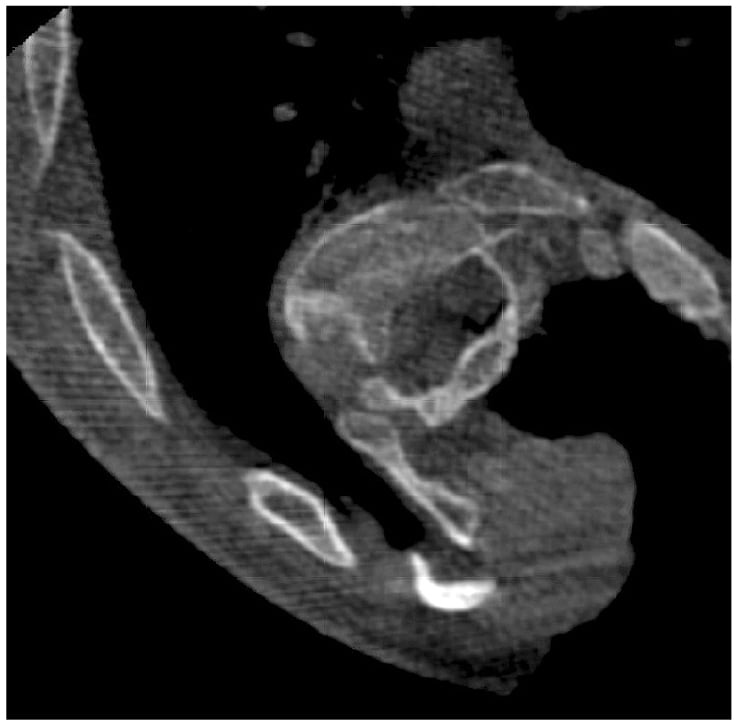

The patient underwent a T2–L4 posterior segmental instrumented fusion with posterior column, or Ponte, osteotomies at T6–L1. The Ponte osteotomies helped to improve the flexibility of the spine, but despite this “softening” of the curve’s apex, it remained relatively stiff, suggesting that translation of the apex toward midline for the correction would be a challenge. Intraoperative 3D fluoroscopy showed significant vertebral body rotation and dysplastic pedicles, particularly near the T8–T11 apex (Fig. 2), which would make challenging the placement of screws at the apex of the curve using standard “freehand” methods and with risk for neurological injury.

Figure 2: Intraoperative 3D fluoroscopy shows 90° rotation of the vertebral body with dysplastic pedicles.